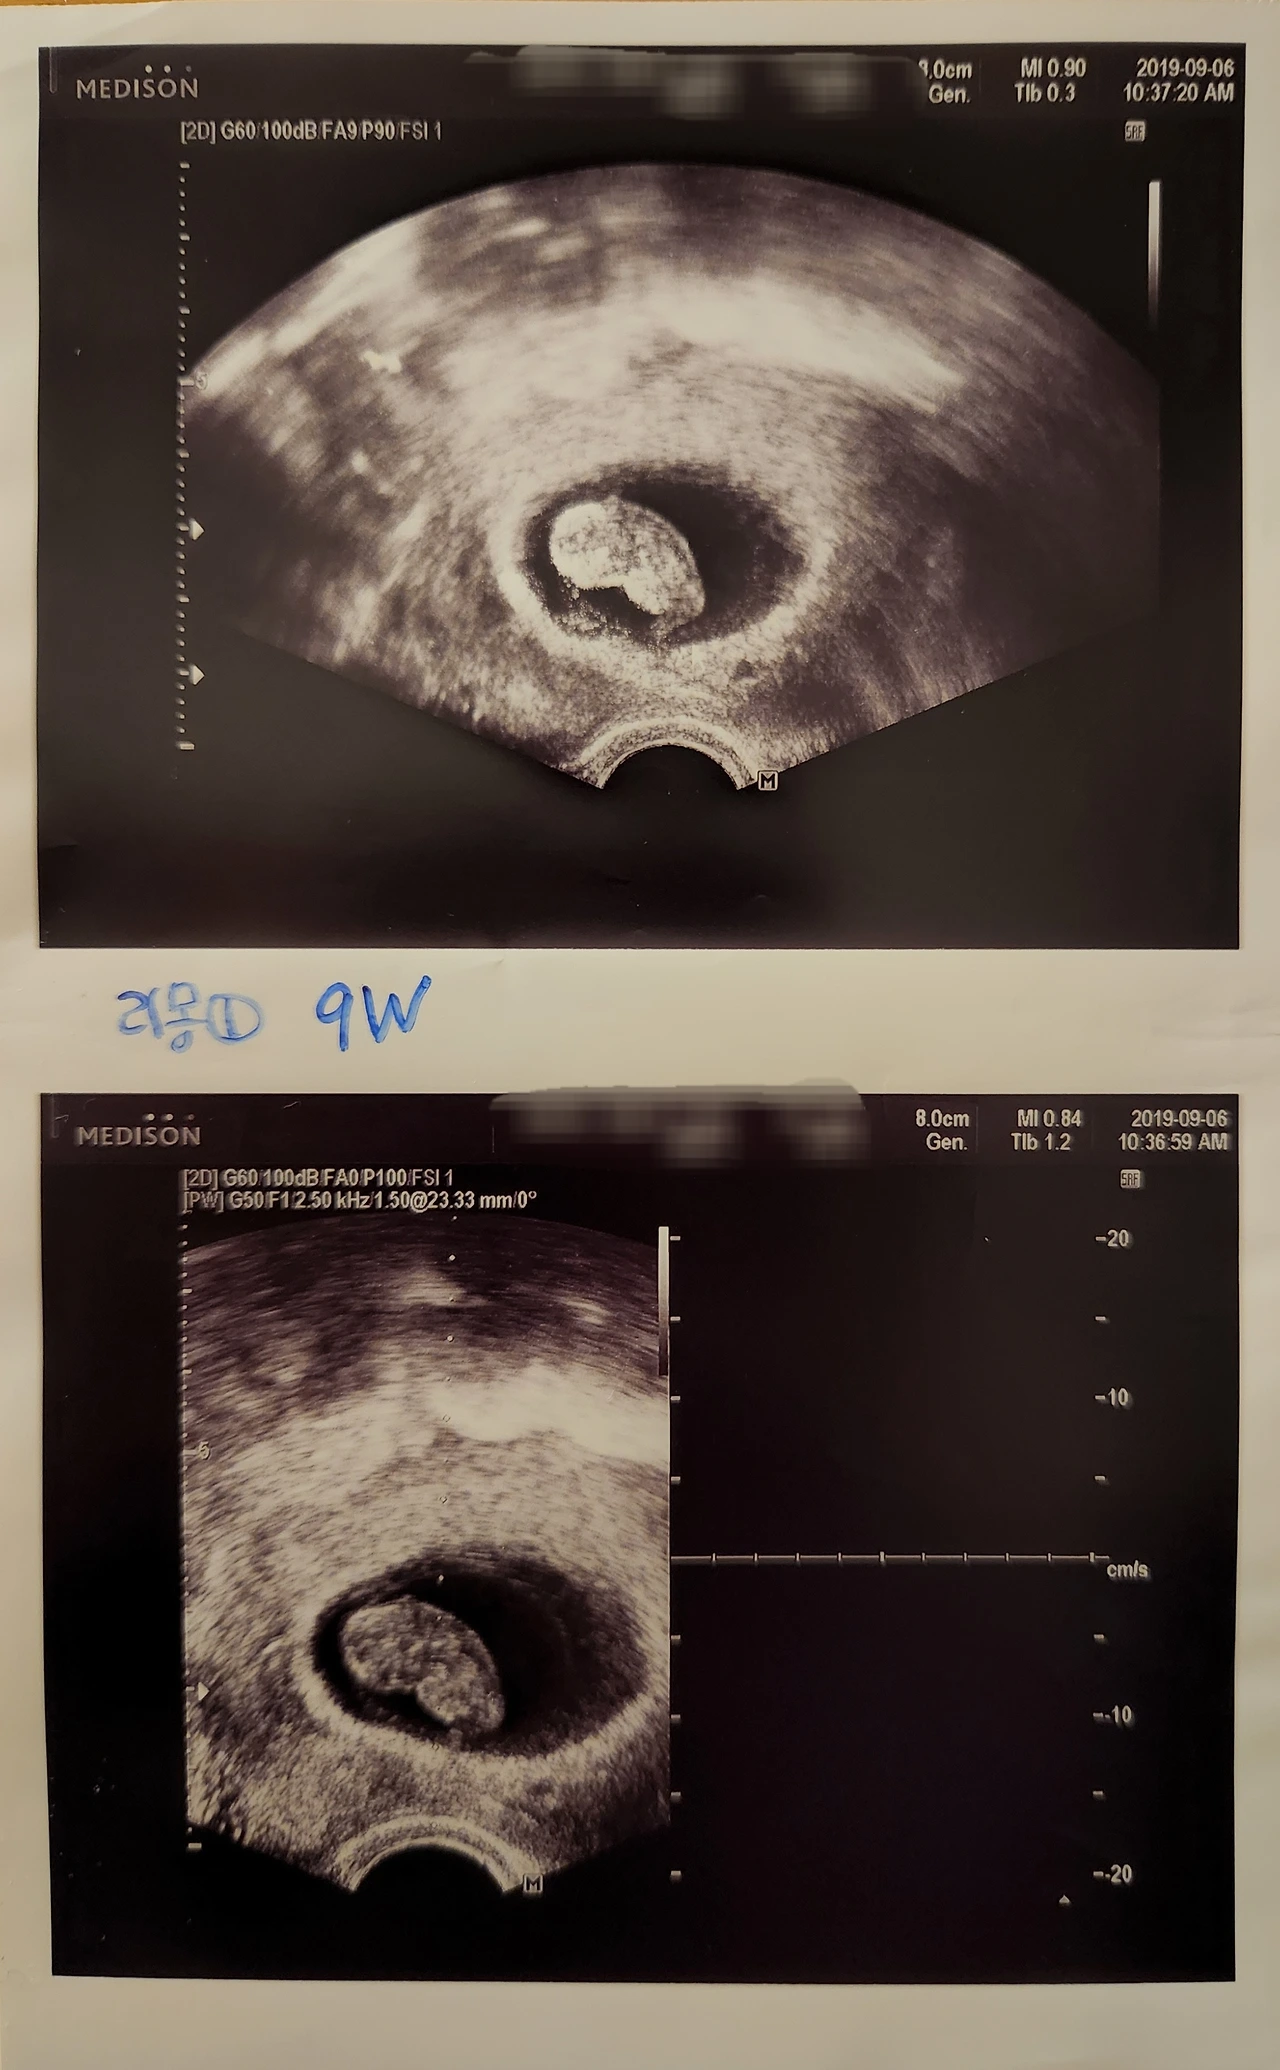

몇 년 전 시험관으로 어렵게 가진 아기를 임신 초기인 9주에 유산했다.

심장이 뛰지 않는데도 초음파 화면 속 양수에서 아무 일도 없다는 듯이 흔들리는 내 첫 번째 아기를 보고 영화 그래비티에서 고요한 우주를 홀로 정처 없이 유영하는 조지 클루니가 생각났다.

의사 선생님은 이미 프린트된 그날의 초음파 사진을 주지 않으려고 했지만 나는 내 첫 번째 아기가 '잊히는 존재'가 아니라 '누군가가 기억해주는 존재'를 만들어주고 싶어서 받아왔고 집에서 그 사진을 끌어안고 하염없이 울다.

둘째이자 태어나기로는 첫째를 임신했을 때 특히 9주까지는 아기가 어떻게 될까 매번 산부인과 검진 시 "심장은 뛰나요?"를 나도 모르게 가장 먼저 물어봤더랬다.